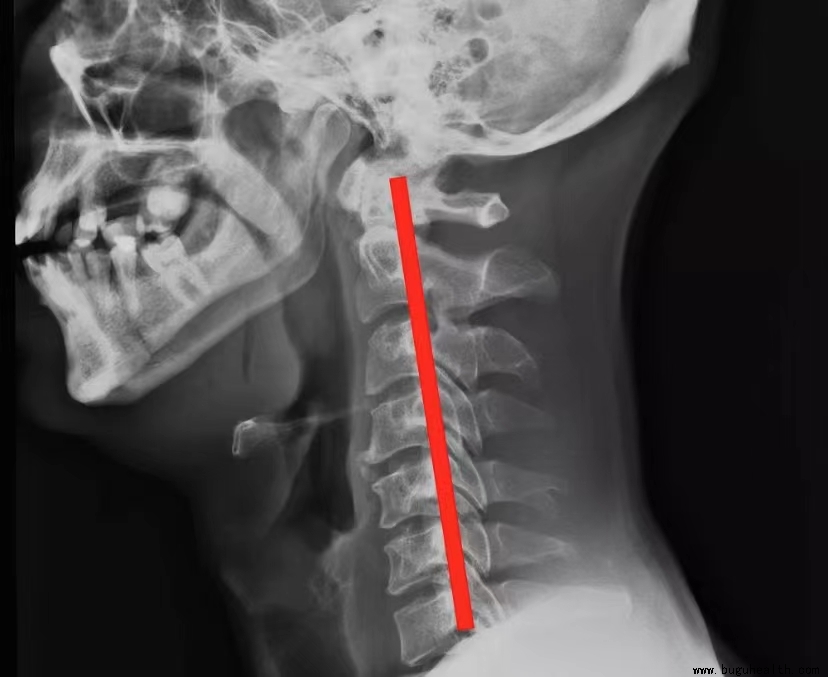

颈椎在正常情况下,有一个向前凸的生理曲度,它能够有效地维持颈椎的正常生理功能,增加颈椎弹性,减轻重力震荡。当这个生理曲度消失,甚至反弓时,就会出现颈椎曲度变直的情况。这不仅会导致颈椎的稳定性下降,还会对脊髓和大脑造成潜在损伤。